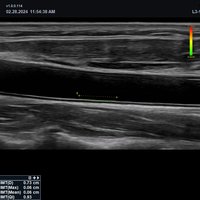

• MSK / Bewegungsapparat

• L3-15H (3-15 MHz) für Ultraschalluntersuchungen in den Bereichen Gefäße, Weichteile, Bewegungsapparat (MSK)

• L3-12H WD (3-12 MHz) für Ultraschalluntersuchungen in den Bereichen Gefäße, Weichteile, Bewegungsapparat (MSK), Pädiatrie